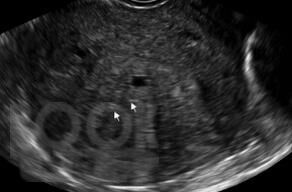

Особенности диагностики различных форм эндометриоза

В учебном пособии на современном уровне освещены вопросы диагностики эндометриоза различной локализации. Предназначено для врачей акушеров-гинекологов с целью формирования научно-обоснованного подхода в диагностике эндометриоза и его локализаций с целью обнаружения заболевания на ранних стадиях и сохранения репродуктивного здоровья женщины.